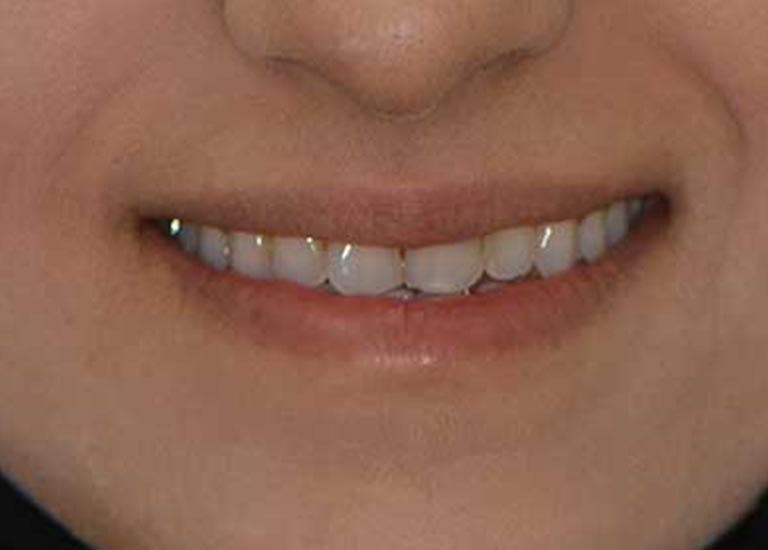

SMILES

AFTER

This patient has suffered from spaces between her lower teeth due to an unknown reason, and by examining the teeth, I found that the gums were healthy and fixed braces were installed and the spaces were closed successfully in addition to the paving of the upper teeth successfully as well.